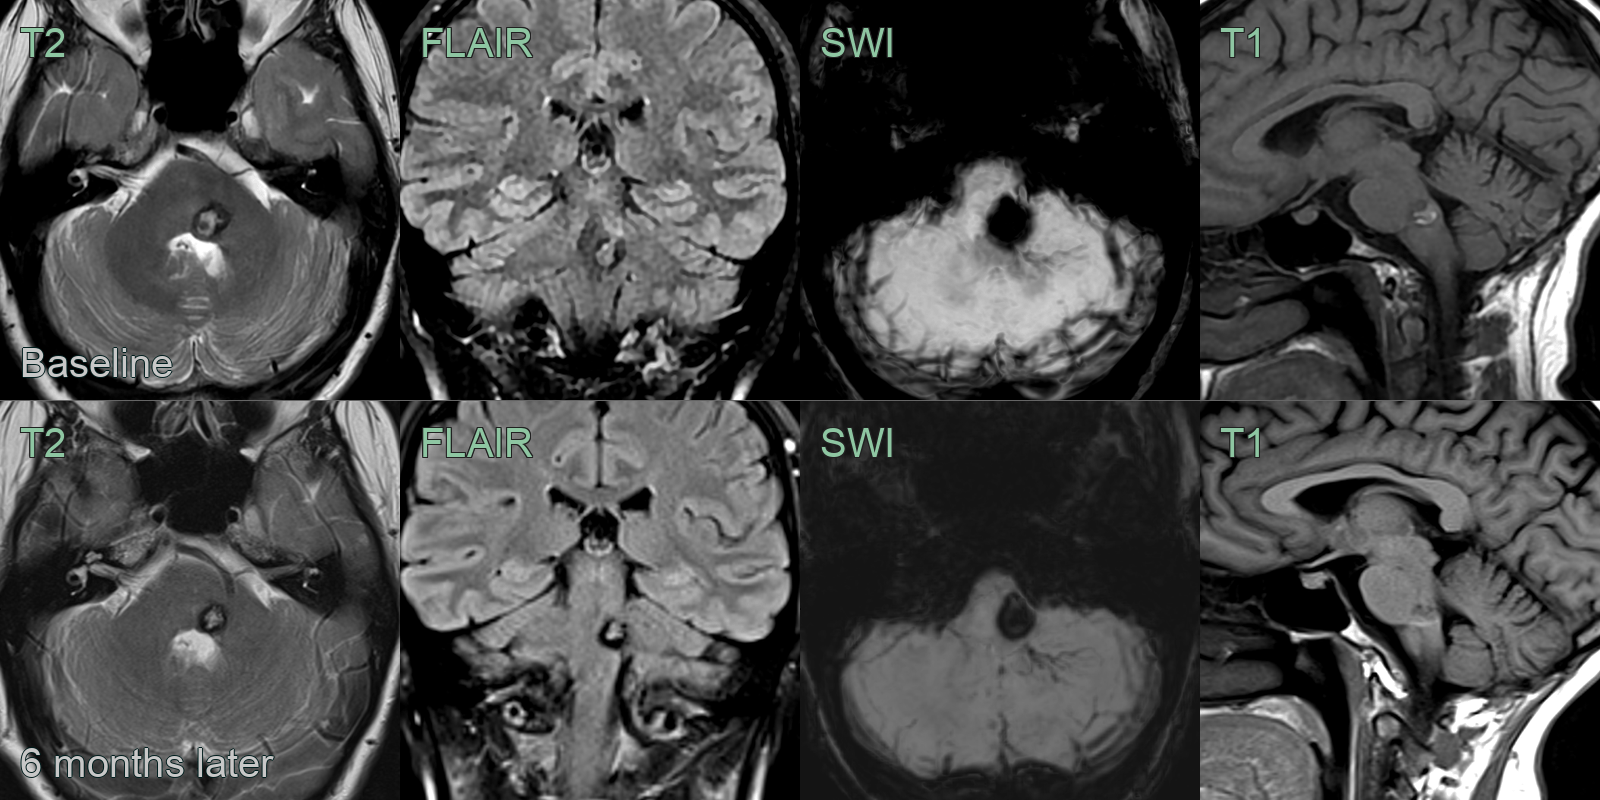

- A 30-year-old presented with left-sided facial weakness and numbness.

- The initial MRI showed a T1- and T2-hyperintense lesion in the left side of the pontine tegmentum, consistent with a recent hemorrhage within a cavernoma. SWI showed a network of small vessels representing an associated development venous anomaly

- 6 months later, mild rim of edema on FLAIR, blooming artefact and T1-hyperintensity had regressed.